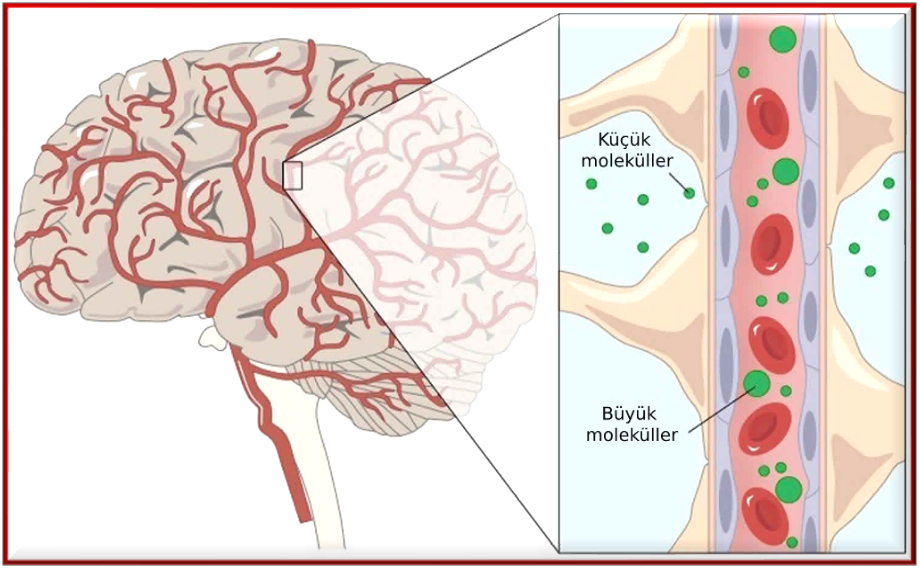

Ayrıca faydalı ve gerekli birçok önemli maddenin kan-beyin bariyerini geçip beyne girebilmesi de yine bir dizi faktöre bağlıdır. Maddenin moleküler ağırlığı, molekülün üç boyutlu yapısını değiştirme yeteneği, hücrenin enzimatik stabilitesi, hücre kaynaklı salgılar, elektrik akımlarına çekim, hidrojen bağlama potansiyelleri, taşıyıcılara çekim ve mevcut patolojik koşulların etkisi bariyerden geçiş vizesi alması için ilk akla gelen faktörlerdir. Daha az etkili faktörler arasında sistemdeki enzimlerin oranı, plazmadaki taşıyıcı proteinlerin bağlanma işlevini yerine getirme kabiliyeti ve serebral kan akışı yer alır.

Genel olarak, taşıma sistemleri kan-beyin bariyerinin iç tarafına bakarken, beyinden kana geçişi sağlayan sistemler bariyerin dış tarafına bakar. Temel maddelerin kan-beyin bariyeri boyunca taşınması basit difüzyon, kolaylaştırılmış taşıma, enerji harcaması ile aktif taşıma ve veziküler taşıma ile gerçekleşir. Lipidlerin çözünürlüğü, geçiş kapasitesi, moleküler ağırlığı ve yükü maddelerin taşınması için önemlidir.

Beynin ihtiyaç duyduğu glikoz ve oksijen ise ayrıcalıklıdır. Kan-beyin bariyerinden kolayca geçerek hücrelere engelsiz bir şekilde girerler. Metabolizmanın bir sonucu olan karbondioksit de bu bariyere takılmadan hızla dışarı atılır. Tamamen farkında olmadığımız bu harika sistem olmasaydı, beyin, dışarı atılamayan karbondioksit nedeniyle şişer ya da şekersizlikten ölürdü.